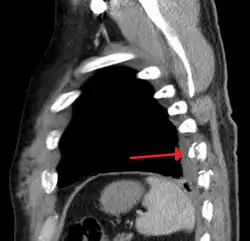

| An X ray showing multiple old fractured ribs of the person's left side as marked by the oval | |

Plain X-rays often pick up displaced fractures but often miss undisplaced fractures.[13] CT scanning is generally able to pick up both types of fractures.[13]

Illustration showing rib fracture at 3rd, 4th and 5th rib -

Right sided pneumothorax and rib fractures -

Two broken ribs as seen on parasagittal CT